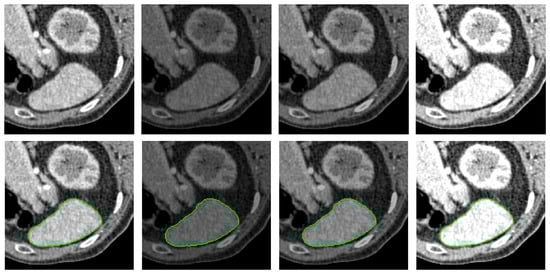

- The PolarMask model does not incorporate contour regularization. In scenarios where image quality is low or distorted by noise, such as in medical CT images, the absence of regularization can lead to unexpected and irregular segmentation results, highlighting significant room for improvement.

- Medical Images: For medical images, we select X-ray computed tomography (CT) scans from [41]. This dataset is commonly used in medical image segmentation evaluations, with image resolution ranging from to pixels, depending on the specific context of each test.

4.2. Qualitative Comparison Analysis

4.5. Performance Under Adverse Conditions